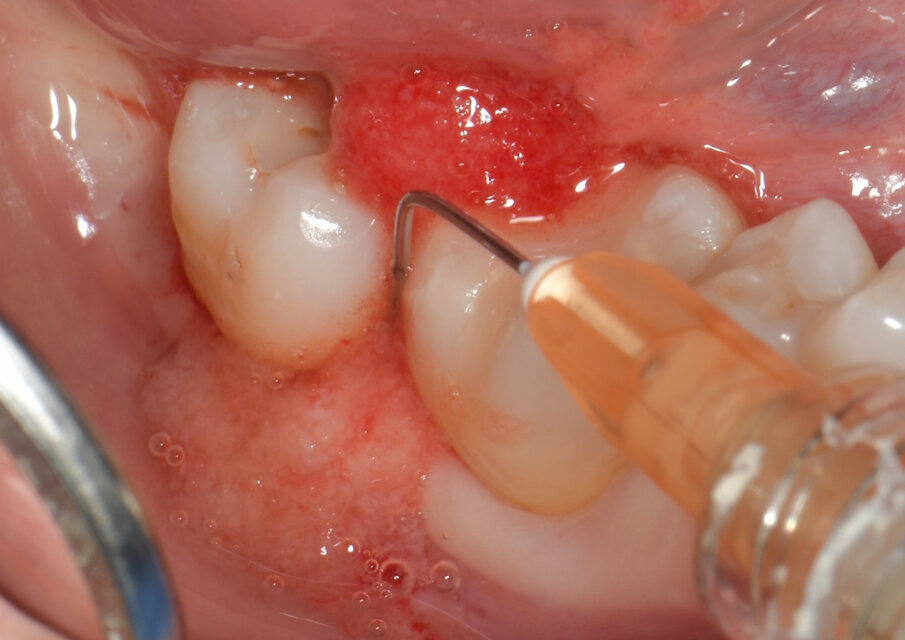

Tutti i pazienti sono stati inizialmente sottoposti a scaling sottogengivale e levigatura radicolare mediante l’impiego di inserti ad ultrasuoni dedicati e curette manuali. In seguito, le tasche sono state riempite con un nuovo hydrogel collagenico in siringa (H42, Bioteck Spa, Arcugnano - Vicenza) (Fig. 1) costituito da collagene di tipo I, polimeri ad alto peso molecolare e quantità ancillari di vitamina C per l’ottimizzazione della reologia. Il prodotto è stato estruso mediante l’impiego di aghi smussi per irrigazione di tasche parodontali con Gauge compreso tra 20 e 25, a partire dal fondo della tasca parodontale, fino a colmarla completamente (Fig. 2). Durante l’estrusione del prodotto e per i successivi 5 minuti (tempo di “setting”), il sito è stato mantenuto asciutto mediante l’impiego di aspiratore chirurgico. In questo periodo di tempo il prodotto diventa più colloso, pur mantenendo un aspetto liquido, tale per cui viene ottimizzata l’adesione ai tessuti connettivali. Nei giorni successivi al trattamento, i pazienti non hanno dovuto osservare particolari accorgimenti nell’igiene dentale e nell’alimentazione.

Fig. 2 - H42 viene applicato partendo dal fondo della tasca fino a colmarla completamente.